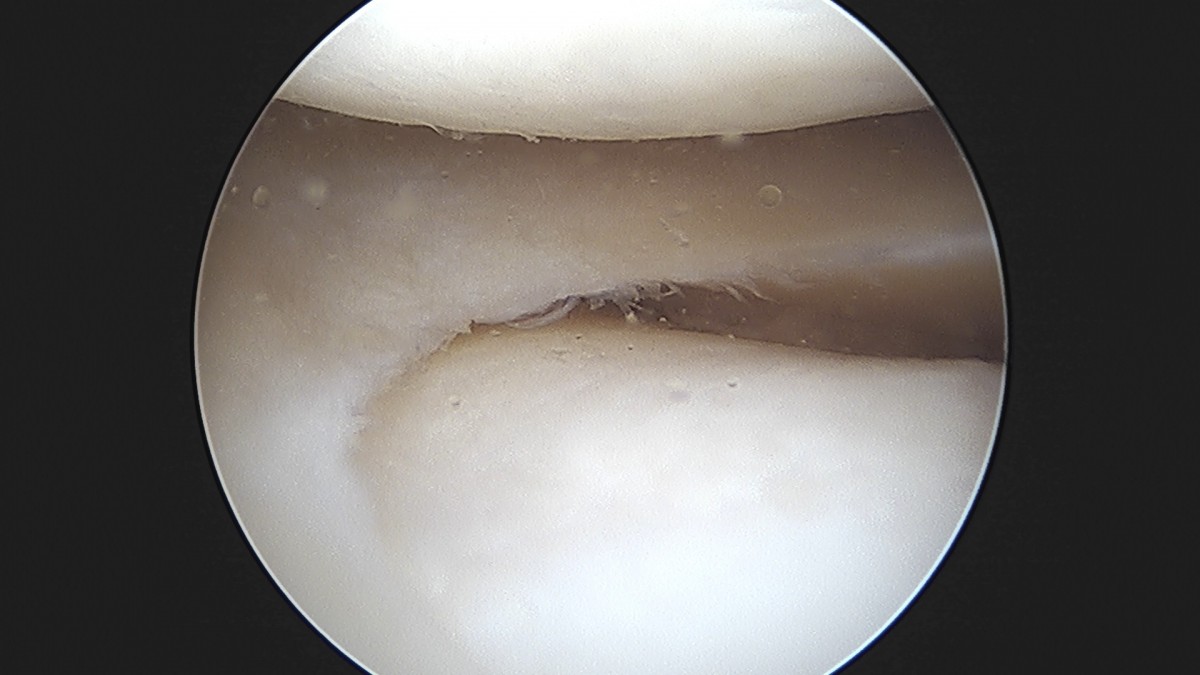

이재상원장님 무릎 반월상 연골판 절제술 장영O 환자

작성자 최고관리자 댓글 0건 조회 369회 작성일 25-09-16 16:02